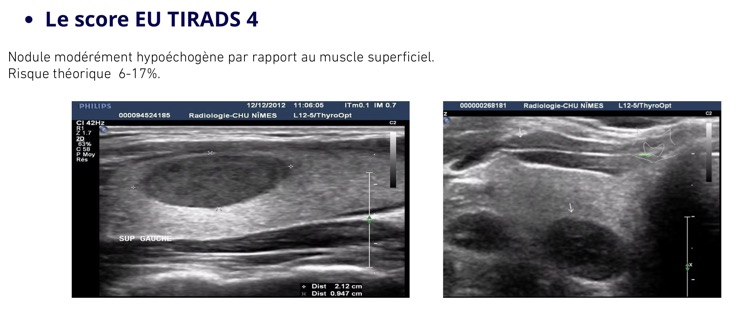

Se méfier des formations hypoéchogènes